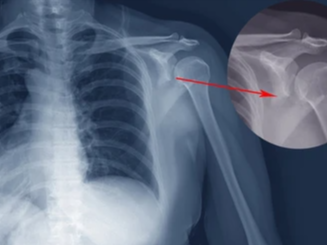

어깨뼈 골절은 어깨 주변을 구성하는 여러 뼈 중 하나가 부러지는 상태를 의미합니다. 어깨는 단순한 관절이 아니라 여러 뼈와 인대, 근육이 복합적으로 연결된 구조이기 때문에 골절의 종류도 다양하게 나타납니다. 흔히 발생하는 골절 위치는 견갑골, 쇄골, 상완골 근위부입니다. 특히 낙상 사고나 교통사고에서는 상완골 근위부 골절이 자주 발생합니다.

이 중에서도 상완골 근위부 골절은 고령자 낙상 사고에서 매우 흔하게 나타나는 골절이며, 경우에 따라 금속 핀이나 금속 플레이트를 이용한 고정 수술이 필요할 수 있습니다.

- 초기 진단

- X-ray 촬영

- CT 검사

- 골절 위치 확인